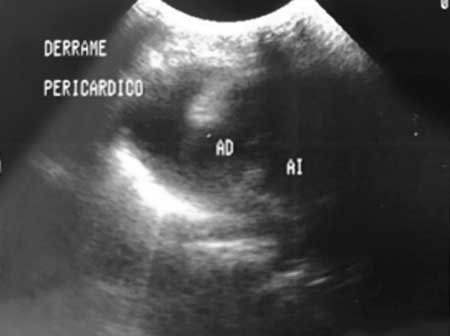

La paciente fue ingresada al Departamento de Urgencias del Hospital Pediátrico de Sinaloa, Culiacán, Sinaloa, México, con disnea de medianos esfuerzos en posición sedente, discreta plétora yugular, sin cianosis ni pulso venoso; a la auscultación se percibió frote pericárdico. En una nueva radiografía de tórax se detectó cardiomegalia (índice cardiotorácico de 0.65). El electrocardiograma demostró elevación difusa de segmento ST, por ecocardiograma (figura 2) se encontró derrame pericárdico (aproximadamente 200 mL). Se realizó pericardiocentesis y se extrajeron 140 mL de líquido de aspecto citrino, con características de trasudado (cuadro 1). Se inició tratamiento con ácido acetilsalicílico (3 mg/kg/día) y antibióticos (cefotaxima y vancomicina) por sospecha de etiología infecciosa.